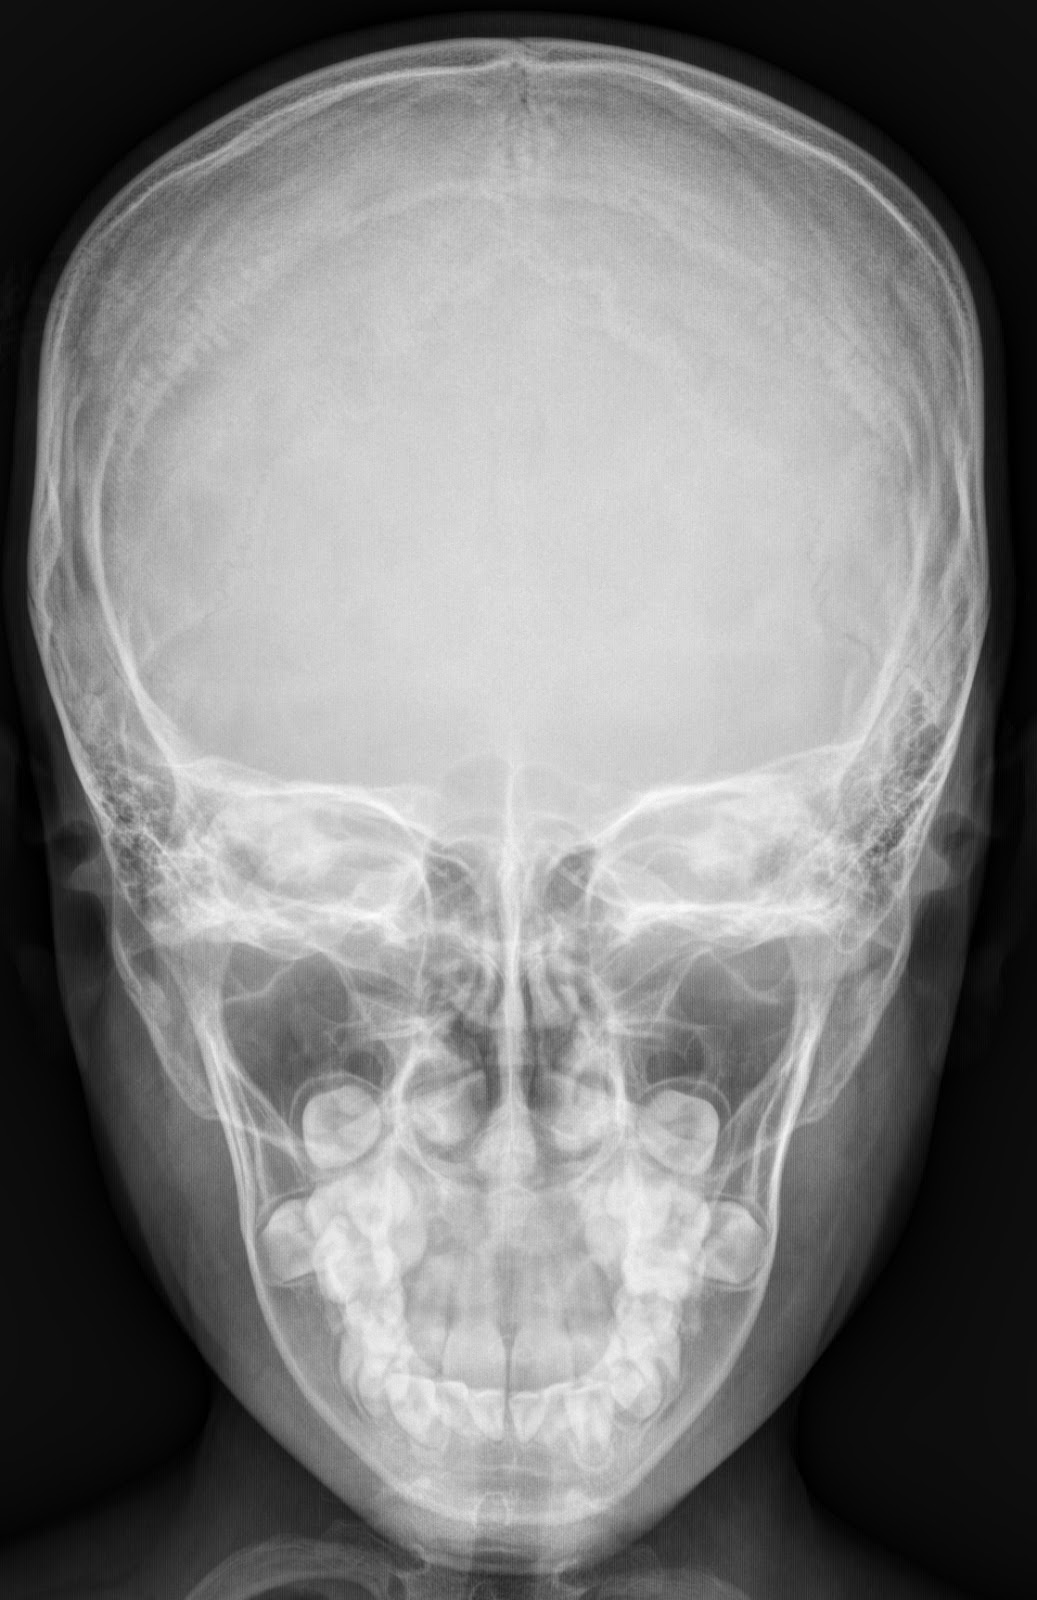

LATERAL AND FRONTAL VIEW OF NORMAL SKULL Side Head Xray The occipitomental (om) 4 or waters view or parietoacanthial projection 2 is an angled pa radiograph of the skull, with the patient. Skull radiography is the radiological investigation of the skull vault and associated bony structures. It's a very effective way of looking at. Temporal arteritis (giant cell arteritis) is where the arteries, particularly those at the side of the. Side Head Xray.

X Ray Cranium Indications soft Tissue Sweling Radiology Imaging